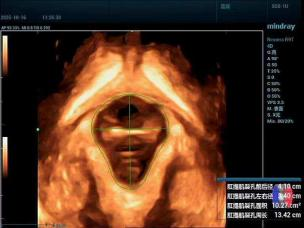

关注盆底健康,为女性保驾护航

除了孕期服务,科室还为女性盆底健康提供专业评估。三维超声可清晰呈现盆底肌肉、韧带等支撑结构,精准测量肛提肌裂孔面积等关键指标,帮助医生早期发现压力性尿失禁、盆腔器官脱垂等问题,为后续康复方案制定与手术评估提供科学参考,守护女性产后及长期健康。